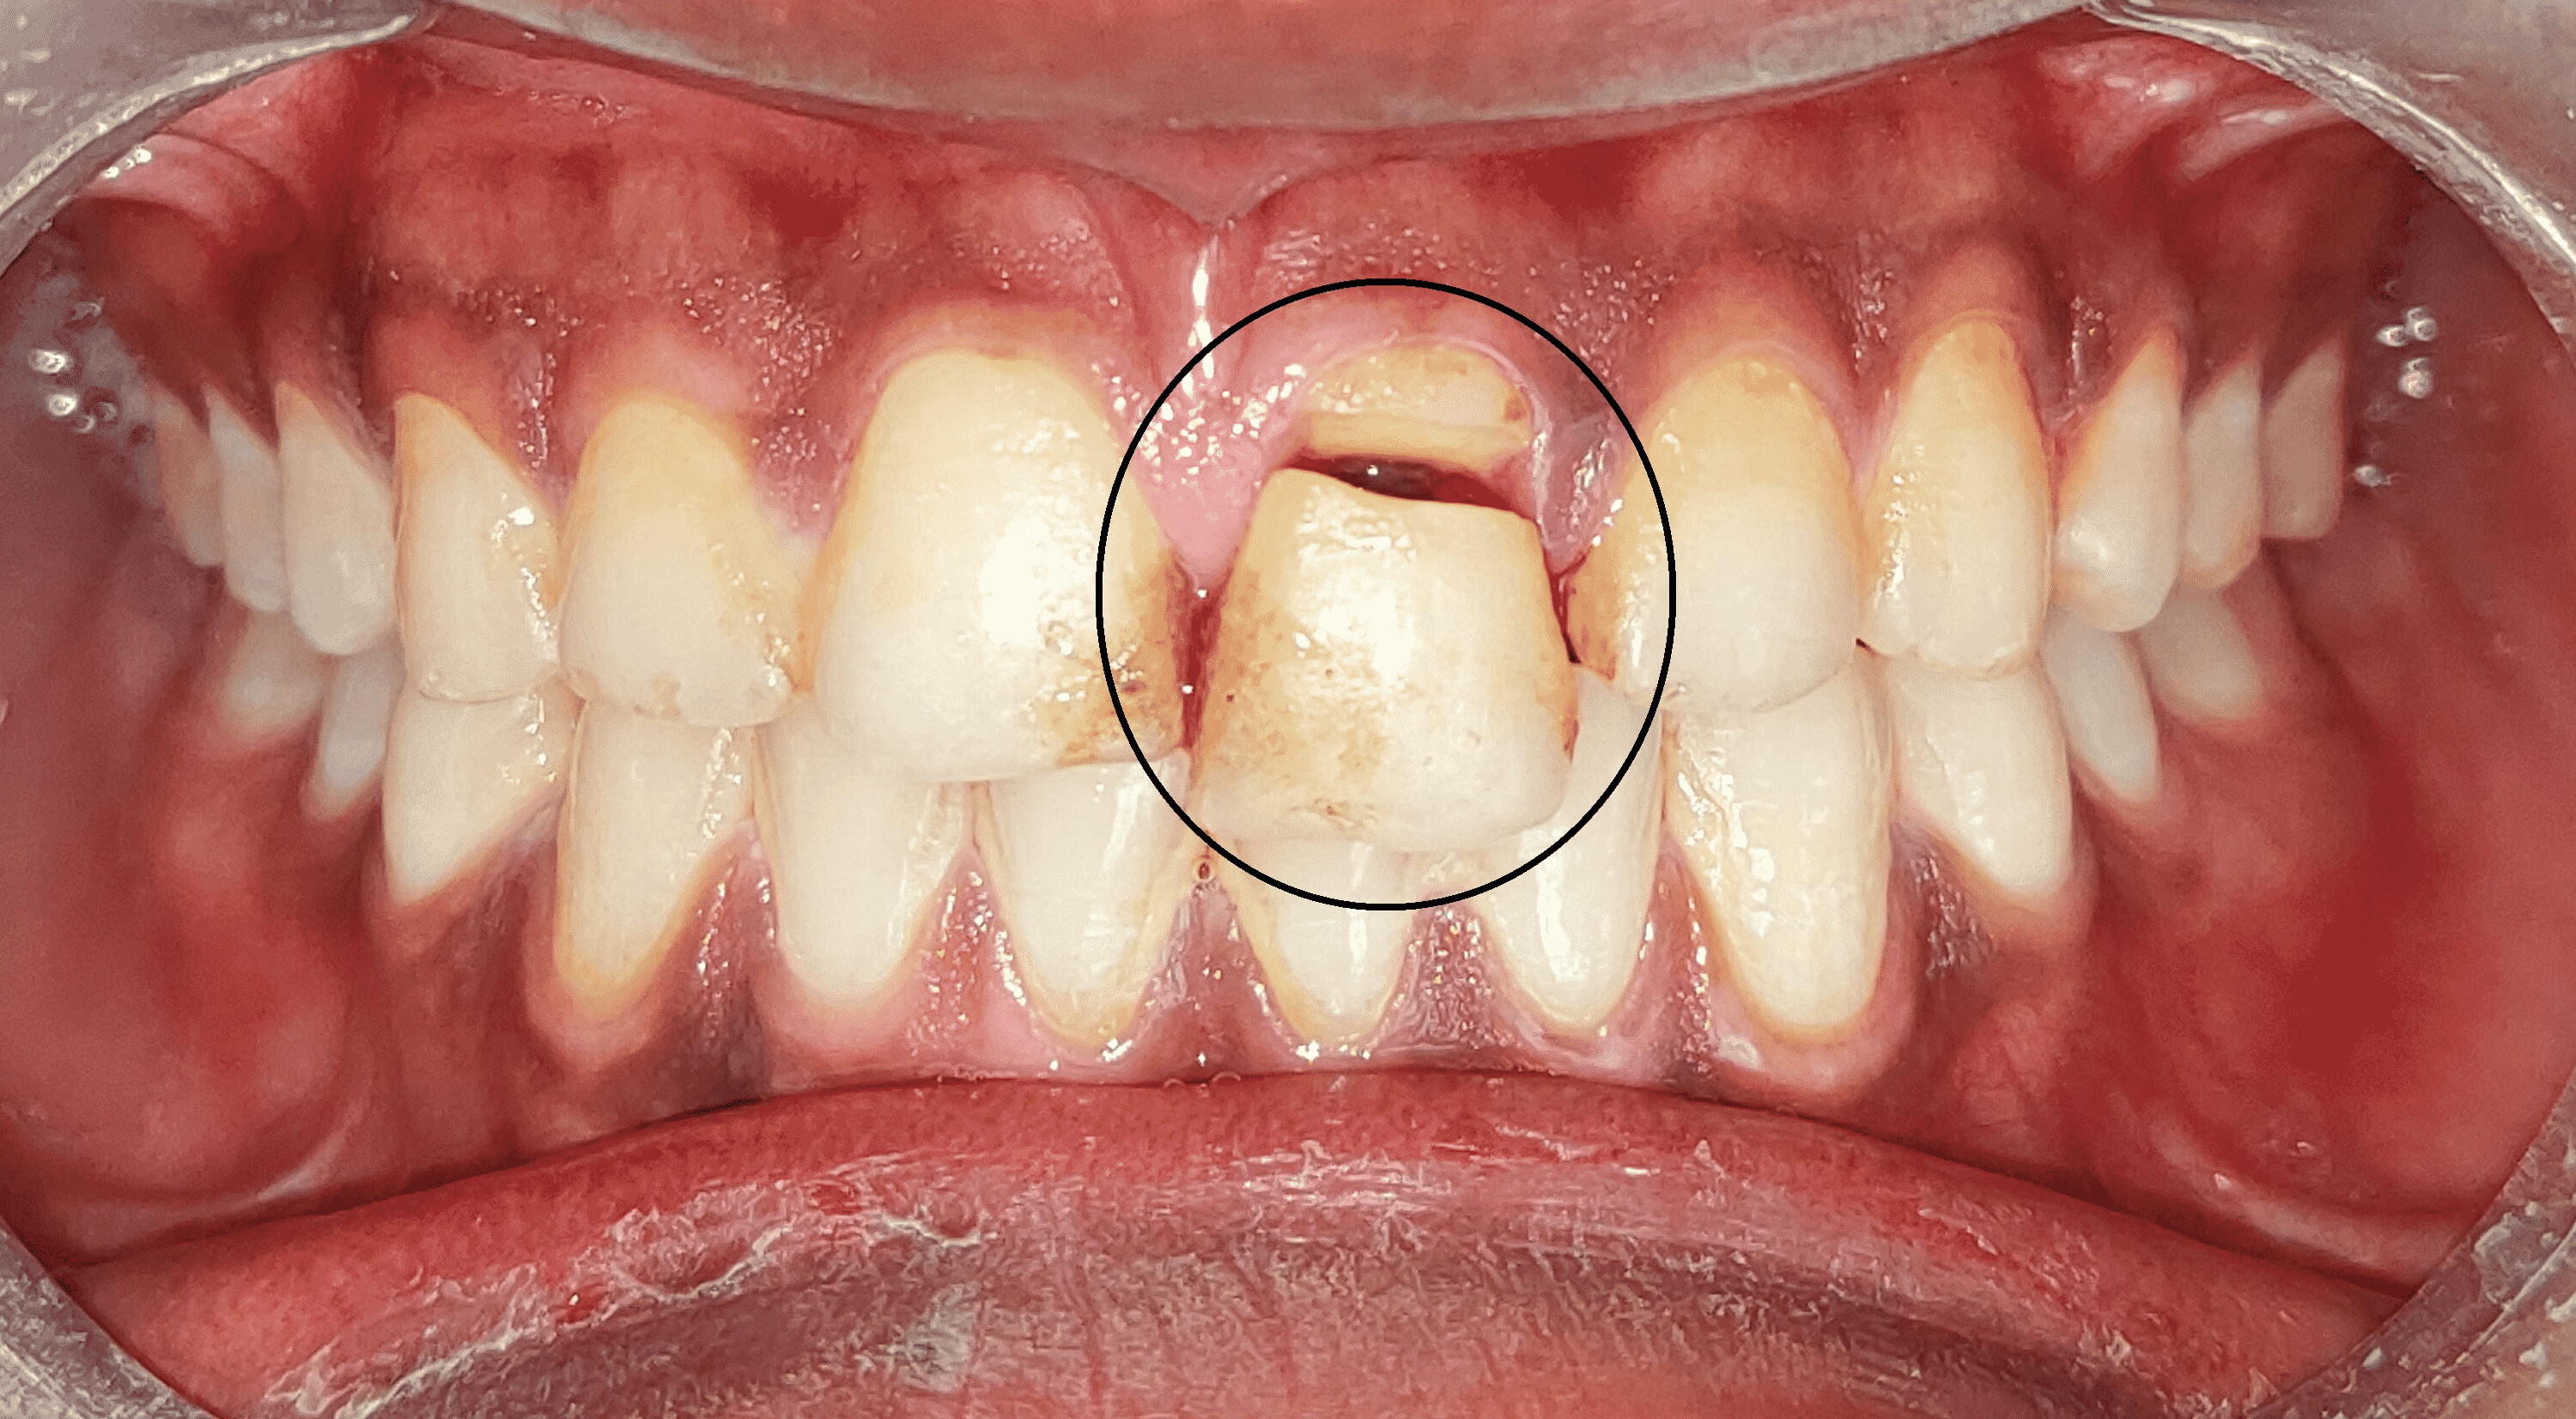

Diagnosis and Treatment of Fractured Teeth

Cusp Tooth Fracture If a crack can be detected, use wedging to test for movement of the. Nonfunctional cusps have been shown to differ from functional cusps in anatomic form, which may lead to the higher fracture potential. A fractured tooth occurs when there is a break or crack in the tooth structure, which can range from minor chips to more. Differentiating a cracked tooth from a fractured cusp or split tooth. This article reviews the diagnosis and treatment of cracked teeth, and explores common clinical examples of cracked teeth, such as cusp. Fractured cusps usually aren’t very painful. If a crack can be detected, use wedging to test for movement of the. See why you should not ignore early warning signs of intermittent tooth pain and sensitivity. Blog post about cracked teeth types, symptoms and solutions. You may have a fractured cusp if a crack forms around a dental filling. Learn how to identify the signs of a cracked tooth, such as pain, sensitivity and discomfort, and how to treat it with an endodontist.